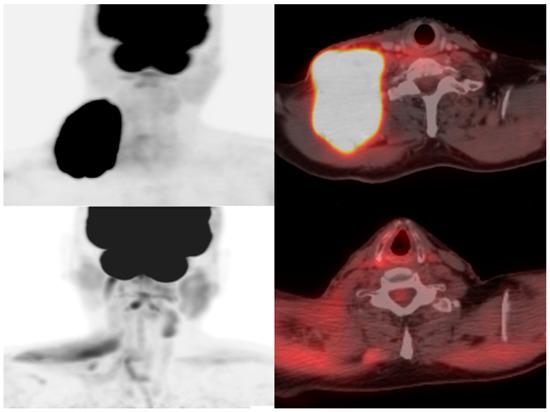

Figure 3.

A 73-year-old man with diffuse large B-cell lymphoma. Maximum intensity projection and axial fused FDG PET/CT pre- (above) and 28 days post- (below) CAR T-cell therapy demonstrating resolution of hypermetabolic adenopathy in the right lower neck consistent with complete metabolic response.

Figure 4.

A 70-year-old man with refractory diffuse large B-cell lymphoma. Maximum intensity projection and axial fused FDG PET/CT pre- (right) and 3 months post- (left) CAR T-cell therapy showing marked decrease in size and FDG uptake of right upper lobe lymphomatous mass invading the right chest wall (arrow). Slight increase in FDG uptake of left upper lobe pulmonary nodule (arrow), also suspicious for lymphoma.